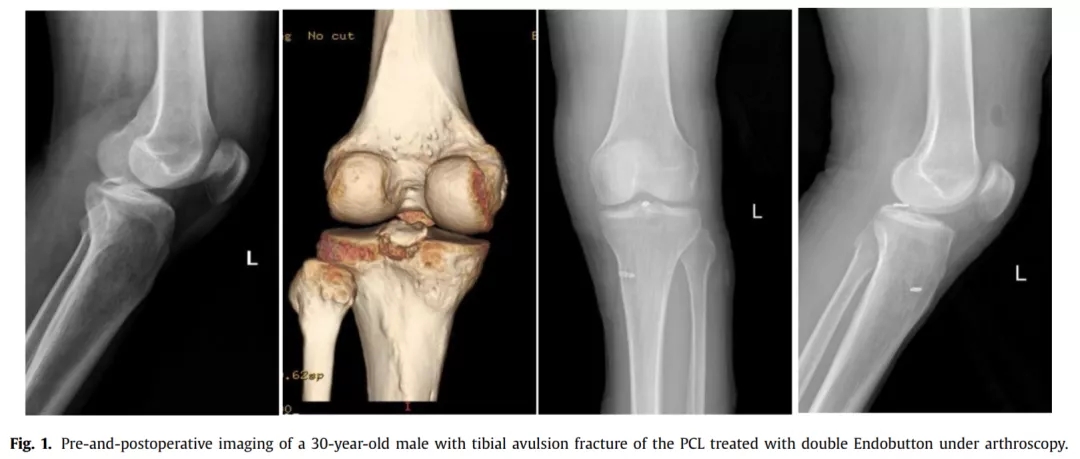

胫骨后叉止点骨折可分为三型,I型为无移位骨折,通常可保守治疗,对II型和III型移位骨折,通常采取手术治疗,以恢复膝关节稳定性。 关节镜下Endobutton固定后叉止点骨折因其微创、固定有效等优点,已成为治疗的首选。但关节镜手术技术要求高,因此,有学者采用自制钩钢板切开复位固定后叉止点骨折,取得了良好效果。结果发表在2021.07 Injury期刊上。